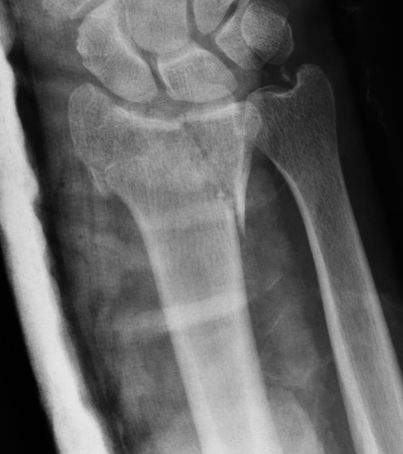

Definition

Intra-articular fractures of the dorsal articular margin of the distal radius

Unstable and allow volar subluxation of the carpus

Management